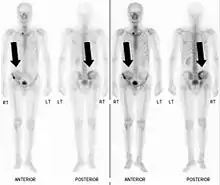

Bone scintigraphy

Bone scintigraphy showing black marks where pelvic bone damage has occurred.

Also known as a bone scan, bone scintigraphy involves the injection of a small amount of radioactive tracer into the bloodstream. This tracer decays and emits radioactive energy which can be detected by a special camera. The camera produces a black and white image where areas shown as dark black indicate bone damage of some kind. If there is a black spot in the lumbar vertebrae (e.g. L5) this indicates damage and potentially spondylolysis. If this test is positive, a CT scan is usually ordered to confirm spondylolysis.[13]